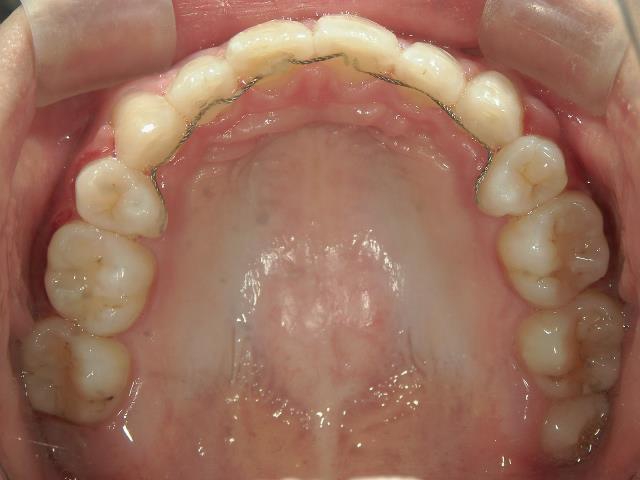

矯正歯科 治療前